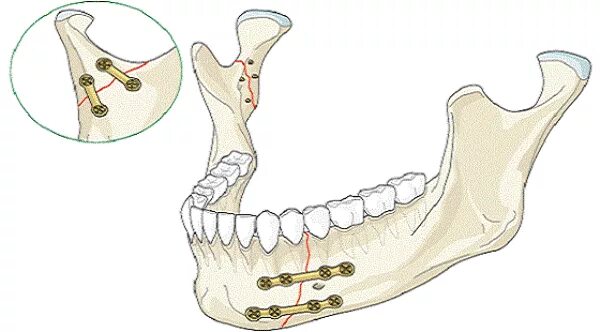

Переломы челюстей студфайл